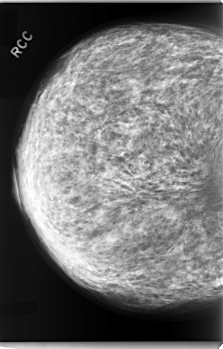

C_0078_1.RIGHT_CC

RIGHT_CC LINES 5920 PIXELS_PER_LINE 3784 BITS_PER_PIXEL 12 RESOLUTION 50 NON_OVERLAY